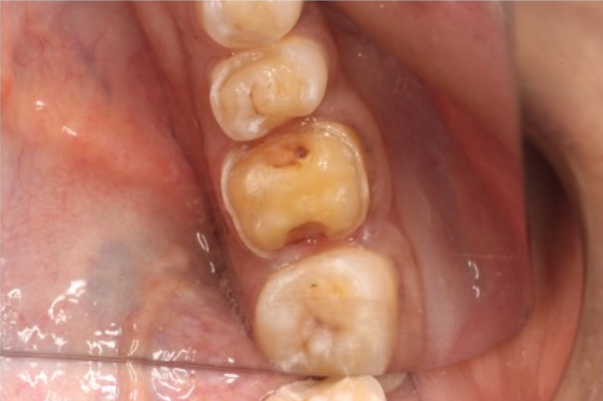

Dental Inlays are equipped to fit and mold in the chewing area of your tooth that has been destroyed or damaged through an injury, decay, or other oral issues. Inlays are advised when a regular filling does not withstand the chewing forces and a crown is too much to protect a dental decay.